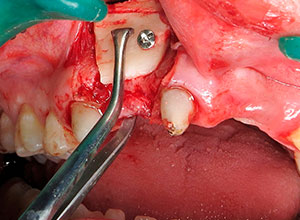

La cirugía se realiza con anestesia local (articaína 4% con 1:100000 de epinefrina). Se realiza una anestesia local del nervio dentario de la zona donadora y una infiltración subperióstica en la zona receptora. La incisión con hoja del no 15 se hace preservando las papilas. Se levanta un colgajo mucoperióstico en la zona receptora preservando las papilas de los dientes adyacentes. Se mide el tamaño de la zona a injertar y se realiza una incisión recta desde el inicio de la rama ascendente mandibular hasta el segundo molar mandibular. Se diseca lateralmente la mucosa hasta lograr exponer la parte posterior del cuerpo de la mandíbula.

Con el Injerto óseo modelado, se procede a colocar en el defecto óseo, fijándolo con tornillos, para asegurar su estabilidad.